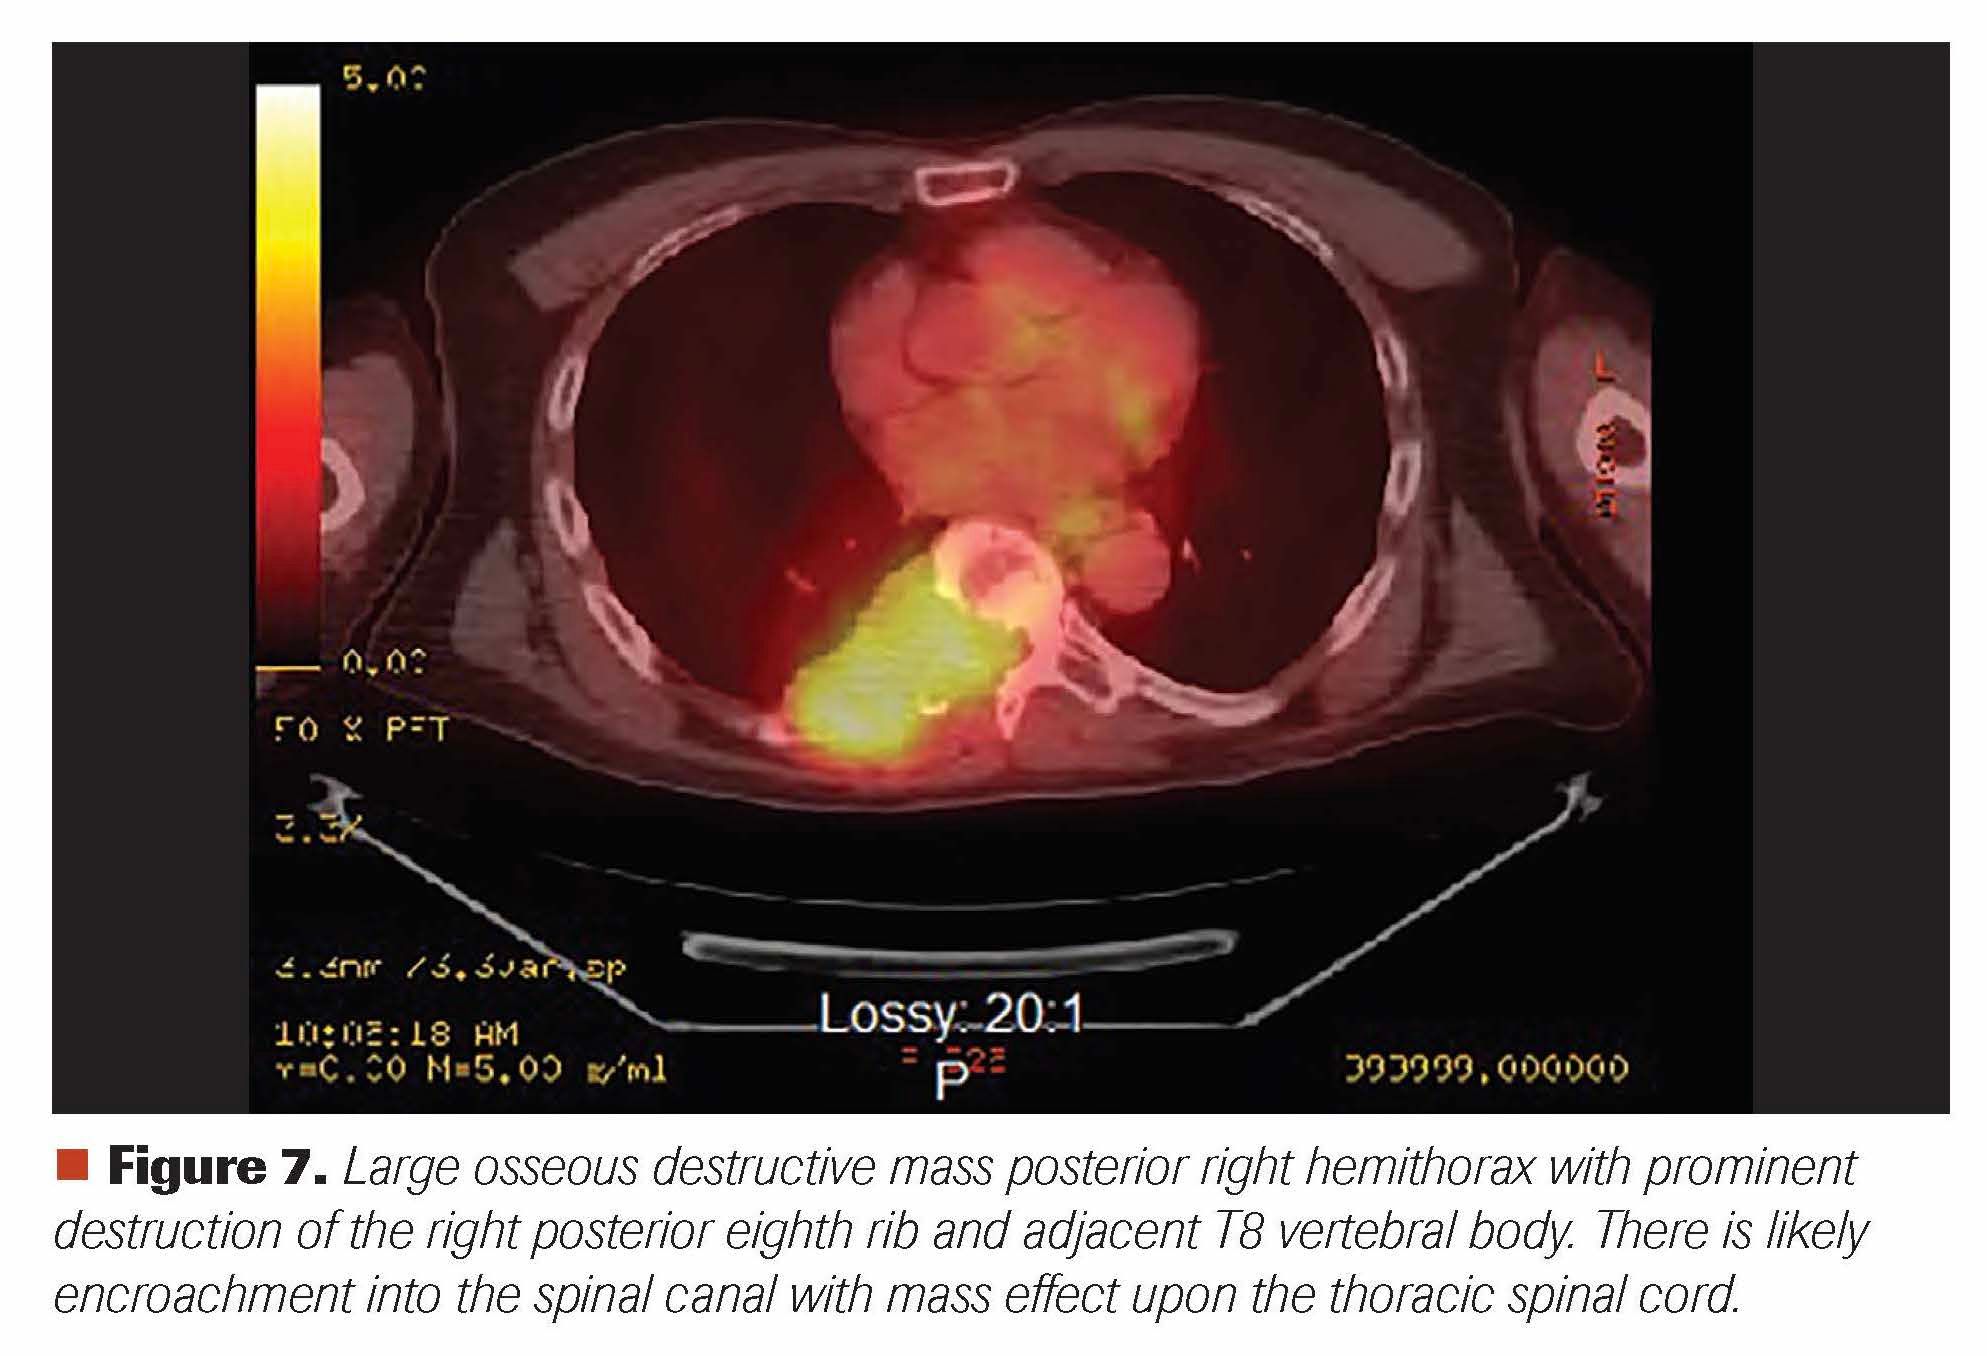

A man aged 65 years presented with right-sided lower thoracic back pain of 1-month duration; it was brought upon by pushing a sliding door in his garage. While it was initially a sharp pain, it transformed into a dull continuous ache radiating to his right rib and right hemithorax. He thought he pulled a muscle and saw a chiropractor, but he received no relief despite 5 chiropractic treatment sessions. During all this time he did not notice any extremity weakness or bladder or bowel incontinence, but he eighth area. He next saw his primary care provider, and a CT scan of his chest revealed a soft tissue mass measuring 6.2 x 3.5 x 2.8 cm in the posterior mediastinum/posterior chest wall with involvement of the posterior eighth rib and adjacent T8 vertebral body, with extension into the right aspect of the spinal canal (Figure 1). Further evaluation with an MRI of the thoracic spine confirmed the T8 compression and associated soft-tissue mass causing moderate-to-severe central spinal stenosis (Figure 2). A CT-guided biopsy of this large destructive mass revealed sheets of plasma cells (Figures 3 and 4). Further work-up revealed abnormal serum protein electrophoresis with a 3.53 g/dL monoclonal serum paraprotein, abnormal serum immunoglobulins (Ig; 5365 mg/dl; IgA, 23 mg/dL; IgM, 11 mg/dL), abnormal free light chains (λ free light chain, 14.6 mg/L; λ free light chain, 146.2 mg/L; ratio, 0.1), and abnormal λ-2 microglobulin of 4.9 mg/L. Bone marrow aspiration and biopsy revealed plasma cell myeloma comprising 40% of marrow cellularity (Figures 5 and 6). Staging work-up was completed with a PET-CT, confirming large osseous destructive mass at T8 level (Figure 7).

Figure 7. Large osseous destructive mass posterior right hemithorax with prominent destruction of the right posterior eighth rib and adjacent T8 vertebral body. There is likely encroachment into the spinal canal with mass effect upon the thoracic spinal cord.